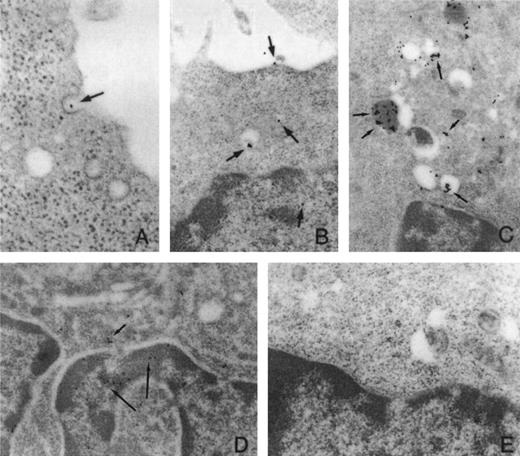

ODN Uptake. (A) ODN is found in clathrin coated pits indicative of receptor-mediated endocytosis. (B and C) ODN can be found in lysosomal (clear vesicles) or endosomal compartments (vesicles filled with darker material); however, some ODN is free and (D) crosses the nuclear membrane to presumably form hybrids with target mRNA. (E) Control panel labeled with Biotin alone. Oligodeoxynucleotides have been decorated with gold beads that appear has black dots in the photomicrograph. Their location is pointed to by black arrows. (Reproduced from The Journal of Clinical Investigation, 1995, vol 95, p 1814 by copyright permission of The American Society for Clinical Investigation.147)